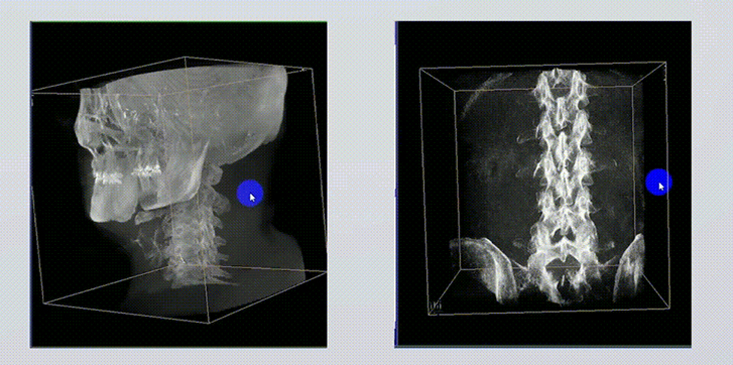

1、術(shù)中實時三維成像

術(shù)中三維成像和橫斷面圖像提供多角度的手術(shù)診斷信息,輔助醫(yī)生進(jìn)行術(shù)中評估判斷,諸如骨折復(fù)位情況和內(nèi)植入螺釘?shù)某叽绾臀恢茫o助手術(shù)更好地完成。

提供更大的術(shù)中三維成像視野,采集更多圖像信息,可一次拍全全段頸椎、全段腰椎、七節(jié)胸椎、雙側(cè)骶髂關(guān)節(jié)、股骨頭及單側(cè)盆骨。